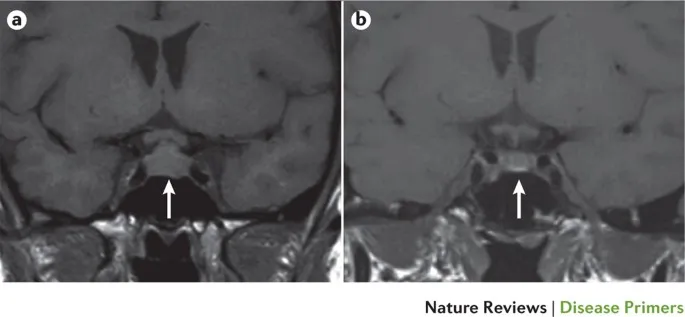

- Diagnosis: Low basal levels of pituitary & target organ hormones (e.g., TSH, free T4, ACTH, cortisol, FSH, LH, estradiol). Provocative hormonal tests. MRI may show an empty sella turcica in late stages.